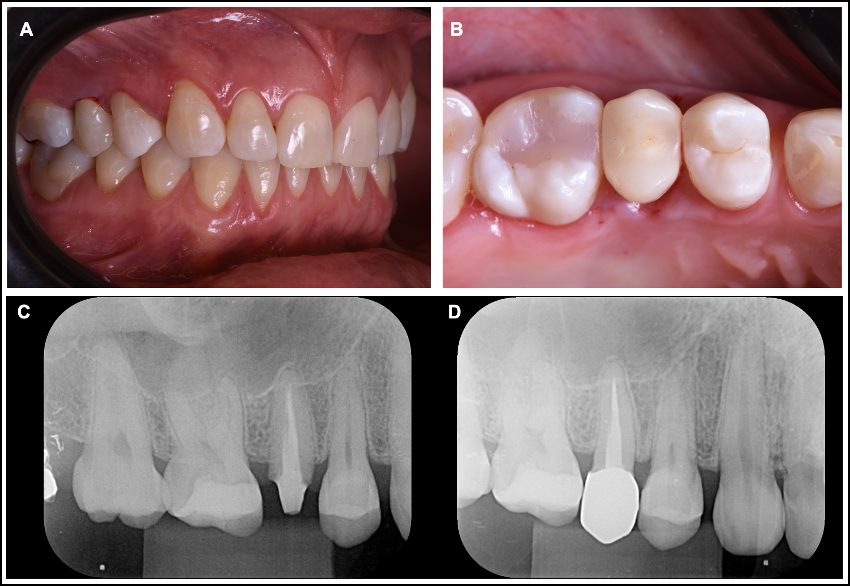

Figura 5. (A) Aspecto final da coroa após os ajustes oclusais e o polimento final; (B) Vista oclusal da coroa finalizada; (C) Rx inicial do paciente com a coroa provisória; (D). Rx final da coroa cerâmica zircônia cimentada com cimento autoadesivo automix Set Maxx (SDI).